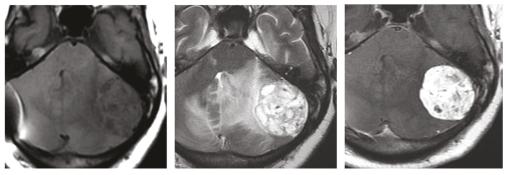

Une femme de 32 ans, sans antécédents pathologiques, consulte pour baisse brutale de l’acuité visuelle. L’examen ophtalmologique trouve un œdème papillaire bilatéral, le reste de l’examen neurologique est sans particularités. Face à cette symptomatologie, un scanner cérébral est réalisé en urgence. Il montre un processus cérébelleux gauche responsable d’un effet de masse sur le quatrième ventricule avec une hydrocéphalie d’amont et des signes de résorption transépendymaire (fig. 1 ). Par la suite, la patiente a bénéficié d’une dérivation ventriculo-péritonéale. Une imagerie par résonance magnétique (IRM) cérébrale a été réalisée pour une meilleure analyse. Elle a permis d’objectiver un processus intra-axial cérébelleux gauche bien limité à double composante kystique et charnue majoritaire en hyposignal T1-hypersignal T2 sans restriction sur la diffusion et se rehaussant de façon intense après injection de chélates de gadolinium (fig. 2 ). La patiente a été opérée (résection en monobloc de la tumeur) (fig. 3 ). Le diagnostic d’hémangioblastome a été confirmé à l’examen anatomopathologique. La patiente s’est améliorée par la suite sur le plan neurologique mais elle a conservé une cécité définitive.